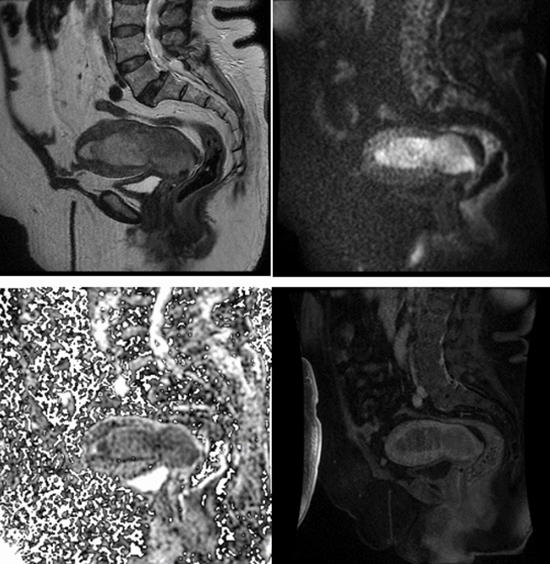

Results In our study, a total of 78 patients with uterine carcinoma were enrolled. the final diagnosis was confirmed as follows: 20 were adenocarcinoma of the cervix, 27 were SCC of the cervix, and 31 were endometrial adenocarcinoma. Certain imaging features were found to be consistent with cervical carcinoma, included parametrial invasion (69.6%), vaginal invasion (66%), stromal invasion (95.7%), and peripheral rim enhancement (68.9%). On post-contrast sequences, cervical cancer appeared hyperintense compared to the myometrium, while endometrial cancer appeared hypointense (96.8%). Endometrial carcinoma was well diagnosed by the presence of an endometrial cavity mass (100%), deep myometrium invasion (>50%) (54.8%), and a greater size in the craniocaudal dimension compared to the transverse dimension (100%).

Discussion The study found that certain morphologic features were reliable indicators for detecting cervical carcinoma, including vaginal, stromal, and parametrial invasions, the presence of hypervascularity and peripheral rim enhancement. On the other hand, myometrial invasion and the presence of a mass in the endometrial cavity were significantly higher in endometrial carcinoma.